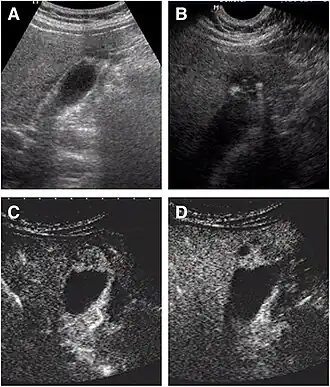

a The fundus of the gallbladder wall was thickened and the GB wall was obscure.

b The intramural echogenic foci were detected by high frequency transducer.

c CEUS—arterial phase (22 s) —heterogeneous hyper-enhancement and wall was intact.

d CEUS—venous phase (34 s) the anechoic spaces were more clear.